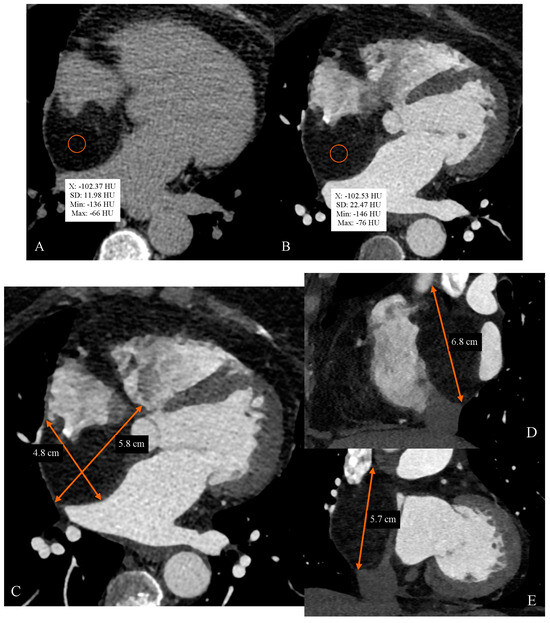

Cardiac Computed Tomography as a Method of Diagnosing the Type of Cardiac Tumor—Example of Interatrial Septal Lipoma Filling the Right Atrium